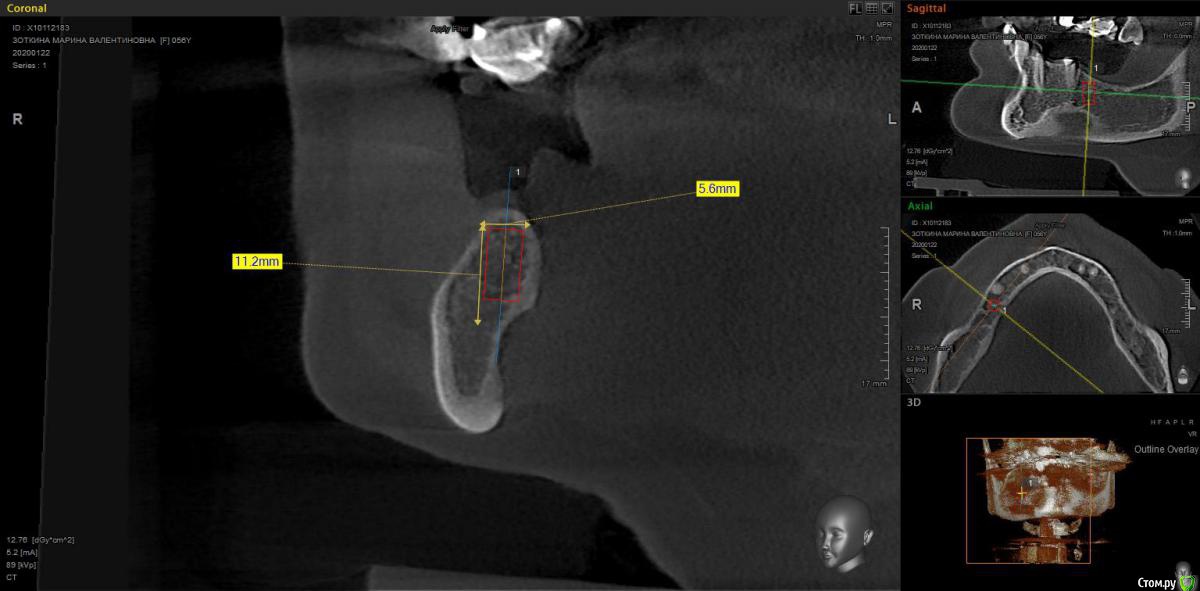

moises Опубликовано 16 февраля, 2020 Поделиться Опубликовано 16 февраля, 2020 Добрый день,коллеги.Планируется имплантация 34,36 и удаление 35, имплантация 45,46 удаление 48.1)Когда лучше убрать 35?одновременно с имплантацией,или допустимо убрать его за неделю-две до?2) 46 зуб- планирую провести НКР вестибулярно(ауто+ксено и резорбируемая мембрана ) и установить 4x8,5 или 4 x 7.3 Neibiotech.Возможности заглубить нет по причине близости нижнечелюстного канала,поэтому,как я понимаю придется установить крестально под заглушку.Тактика верная в этой ситуации? Ссылка на комментарий

moises Опубликовано 16 февраля, 2020 Автор Поделиться Опубликовано 16 февраля, 2020 1) не думаю, что есть какая-то разница, но одновременно будет комфортнее пациенту 2) если 4.6 это второй срез, а у Neobiotech конус, то 4х8 туда входит нормально, но не поскупитесь на стт вестибулярноКонус.То есть при ширине гребня 5,5(если считать в том месте,где планируется платформа) в боковом отделе рекомендуете ограничиться только мягкими тканями? Ссылка на комментарий

VladZp Опубликовано 16 февраля, 2020 Поделиться Опубликовано 16 февраля, 2020 Удалять одновременно Там 4.0*8.5 смело влезет без пластик даже. Кт ж не идеально точное ) 1 Ссылка на комментарий